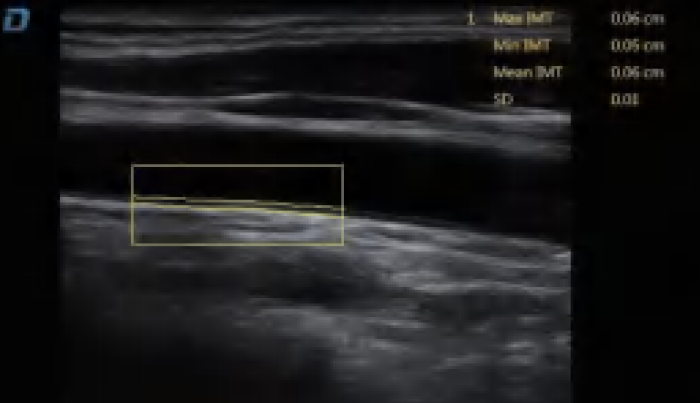

El DW-L50 Exp, impulsado por la avanzada plataforma de ultrasonido ST-U, ofrece imágenes ultra claras en todo momento. Con una movilidad y adaptabilidad sobresalientes, funciona de manera fiable en diversos entornos clínicos complejos. Su introducción permite que más instituciones médicas accedan a tecnología de ultrasonido rentable y de alto rendimiento.